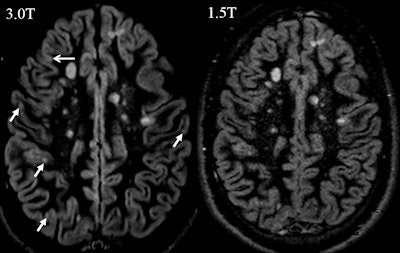

In neuroradiology, the benefits of 3-tesla are quite obvious, not only to obtain better quality routine structural imaging (e.g. of inflammatory lesions), but especially for applications with inherently low SNR, such as susceptibility weighted imaging (SWI), MR angiography (MRA), diffusion tensor imaging (DTI), functional MRI (fMRI), and MR spectroscopy. "However, still up for debate is the crucial question of the diagnostic relevance of 3-tesla MRI, or in other words, 'Does 3-tesla MRI lead to a more sensitive (earlier) and/or more specific diagnosis of certain diseases?' " the authors wrote.

"It has been conclusively shown that 3 tesla shows more (small) inflammatory white and gray matter lesions and offers a better visualization of smaller arterial branches on time-of-flight and contrast-enhanced MR angiography. Despite the fact that this might not lead to an earlier diagnosis of multiple sclerosis, or an earlier detection of aneurysm or vessel malformation with significant therapeutic consequence, (neuro)radiologists would opt for the better image quality if this came at the same cost and level of safety, because it makes the reading procedure easier and more reliable," the authors added.